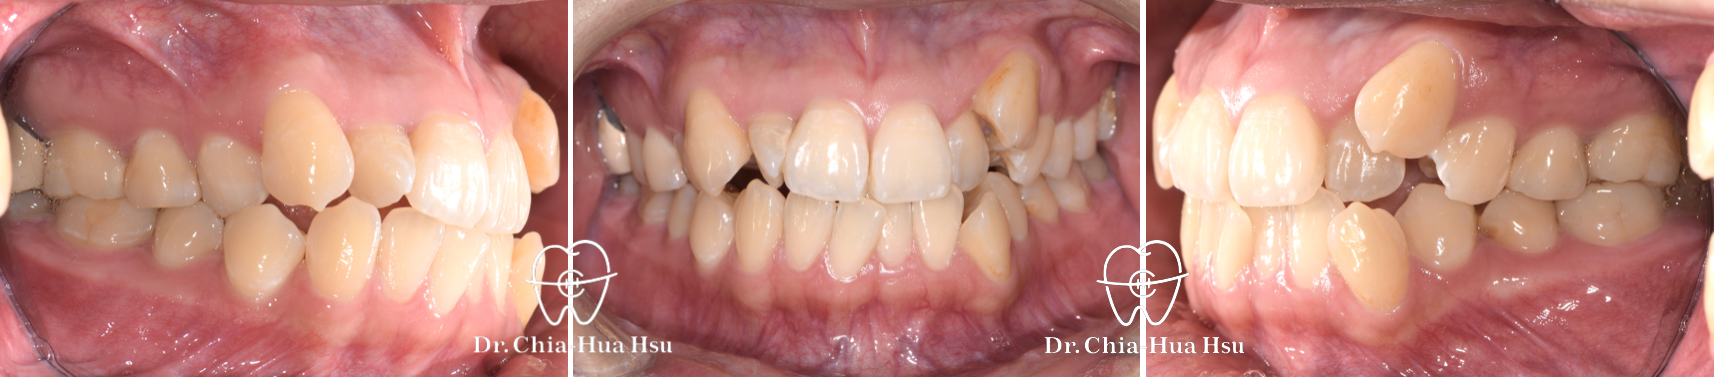

治療前

治療後